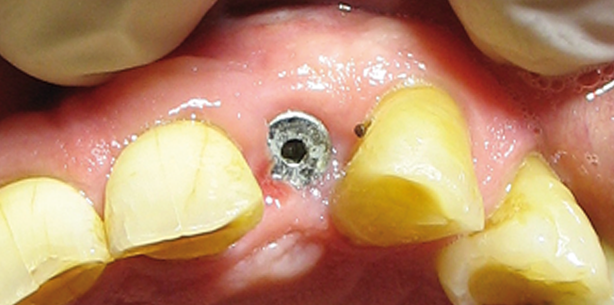

Eine Woche später wurde die Marylandbrücke eingesetzt und es konnte sich dem Zahn 12 gewidmet werden. Da die Verhältnisse unter der Gingiva unklar waren, wurde sich für einen Dreieckslappen entschieden. Mesial dehnte er sich nur bis zur Papilla des Zahnes 11 aus, ohne sie vollständig zu lösen. Distal reichte der Lappen bis zur distalen Papilla des Zahnes 13. Um die Papilla nicht anzuheben, wurde unter die knöcherne Unterstützung 45 Grad nach distoapikal geschnitten und noch in der keratinisierten Gingiva vertikal bis zur mukogingivalen Grenze entlastet (Abb. 10). Die Darstellung des Defektes zeigte einen Krater ohne horizontalen Knochenverlust. Der Krater reicht distal bis zum Paradontium des Zahnes 13. Der vertikale Defekt war ca. 3 mm und die bukkale Wand sehr ausgedünnt, aber noch intakt. Das Infiltrationsgewebe wurde vorsichtig entfernt (Rosenbohrer und Ultraschall) (Abb. 11). Die Implantatoberfläche wurde mit speziellen Bürsten gereinigt. Anschließend wurde sie mit Oxytetracyclin für fünf Minuten dekontaminiert (Abb. 12). Der Spalt zwischen Implantat und bukkaler Wand (1–1,5 mm breit) wurde mit HA auf-gefüllt. Zusätzlich wurde eine dünne Schicht HA (1 mm) auf die bukkale Lamelle gelegt (Abb. 13). Der Defekt wurde mit einer langsam resorbierbaren Membran (24 Wochen) bedeckt. In derselben Sitzung wurde der Approximalkontakt zu 13 verkleinert und nach koronal reduziert. Der Interdentalraum wurde apikal des Approximalkontaktes verbreitert. Der Verschluss erfolgte wie im zweiten Quadranten.

Nach vier Monaten wurde das Implantat 22 freigelegt (Abb. 14–17). Zu diesem Zeitpunkt war das Implantat 12, nach erneuter klinische Untersuchung, unauffällig und ohne pathologischen Befund. Ein Standard-Gingivaformer wurde an 22 für zwei Wochen inseriert. Nach weiteren zwei Wochen wurde die definitive Krone auf ein Standardabutment eingesetzt (Abb. 18).